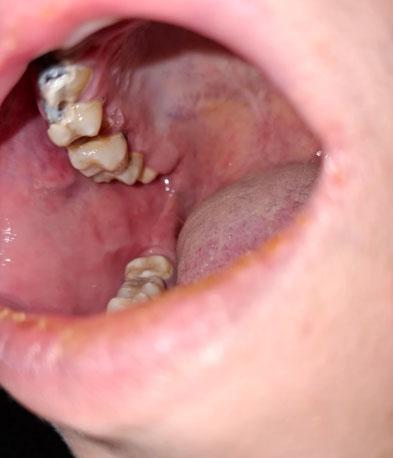

What Is Seen in This Case?

The image shows visible decay on back teeth (molars), with damaged tooth structure and discoloration. The surrounding gum tissue appears slightly irritated, which may indicate early inflammation caused by trapped bacteria.

Back teeth are more prone to decay because they are harder to clean and have deep grooves that trap food and plaque.